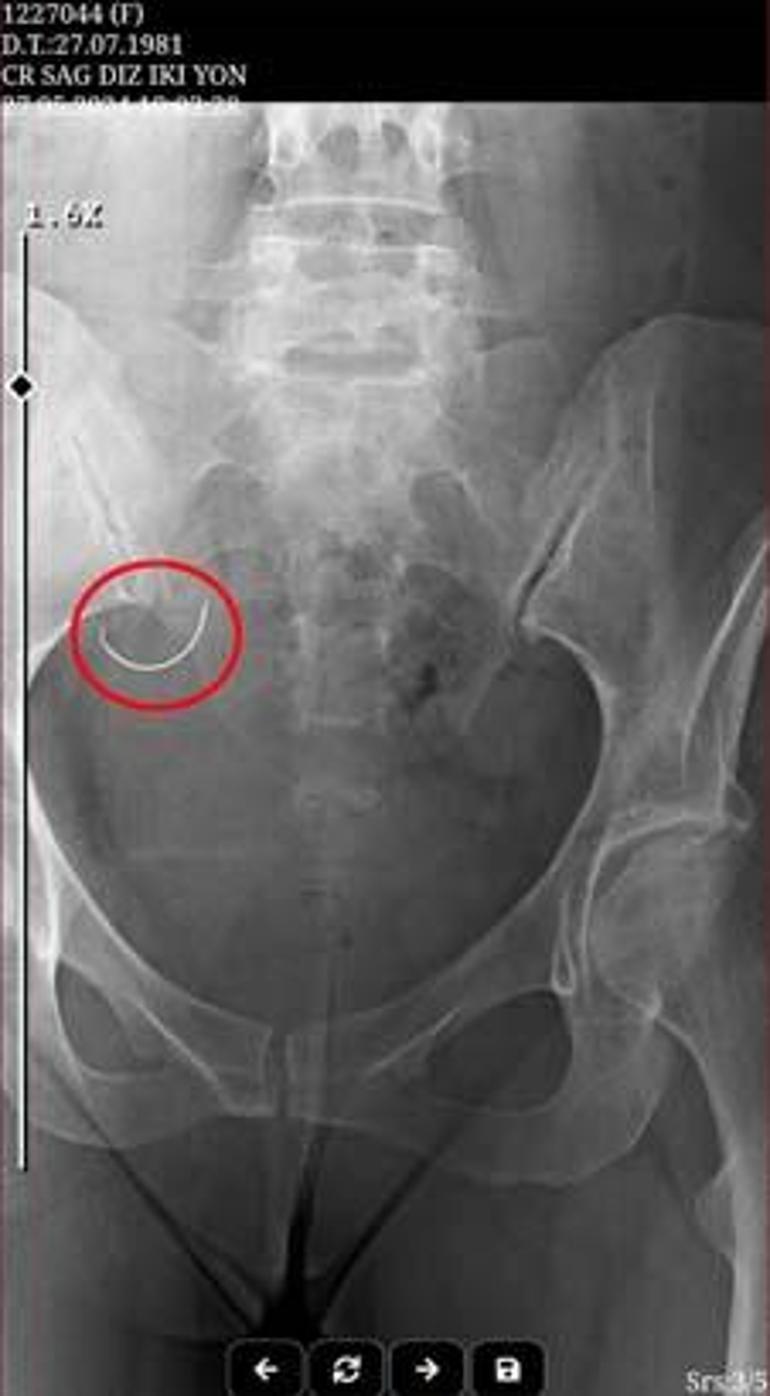

Operasyondan sonra Sabiha İ., şiddetli ağrılar yaşamaya başladı. Sabiha İ., ağrı nedeniyle tüp bebek tedavisi için gerekli ilaçları kullanamadı. Ü.İ., teze nazaran bebek sahibi olamadıkları gerekçesiyle suçladığı eşine, 26 Mayıs 2024 tarihinde fizikî ve ruhsal şiddet uyguladı. Sabiha İ. olaydan 1 gün sonra isimli muayene için gittiği Kumluca Devlet Hastanesi’nde, karnında ameliyat iğnesi unutulduğunu, röntgen sineması sayesinde öğrendi. Hekimlerin sevk ettiği Antalya Eğitim ve Araştırma Hastanesi’nde yapılan ameliyat ile Sabiha İ.’nin karnındaki iğne alındı.